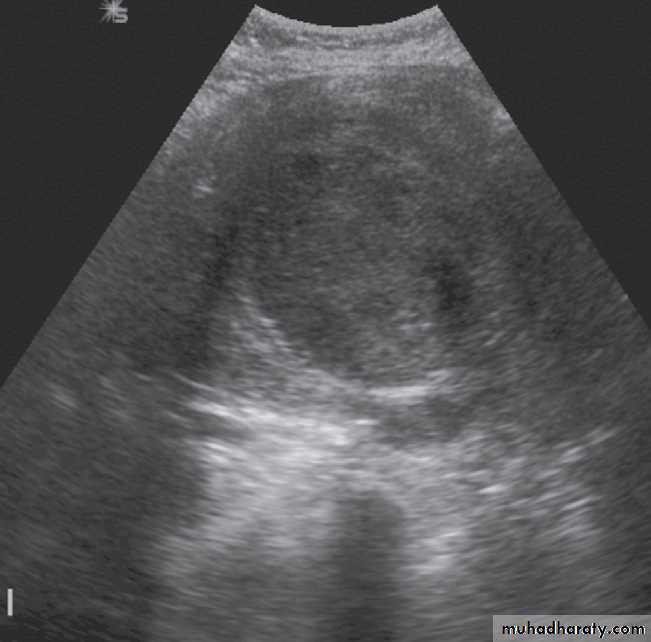

At ultrasound ,the mass may be either hypoechoic or echogenic .

The commonest ovarian tumours are the cystadenoma and the cystadenocarcinoma. Ovarian tumours can be predominantly cystic, solid or a mixture of the two .On ultrasound, the recognized features of benign lesions and malignant lesions are :